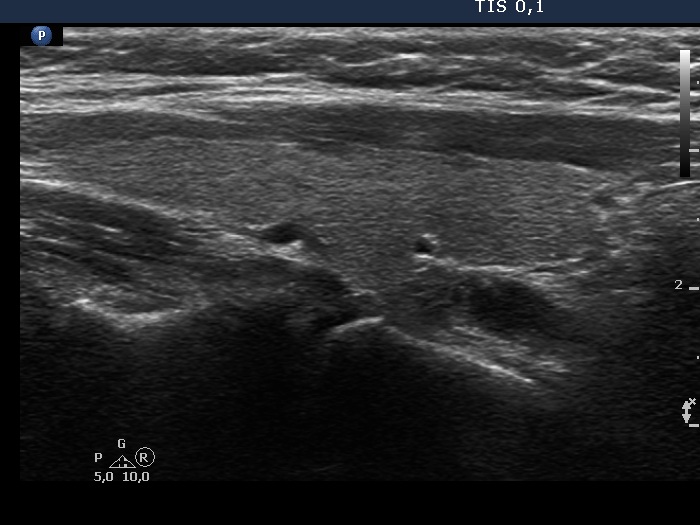

Parathyroid lesions - case 324 (ultrasonographic picture 3)

Right lobe,another longitudinal view, enlargement.